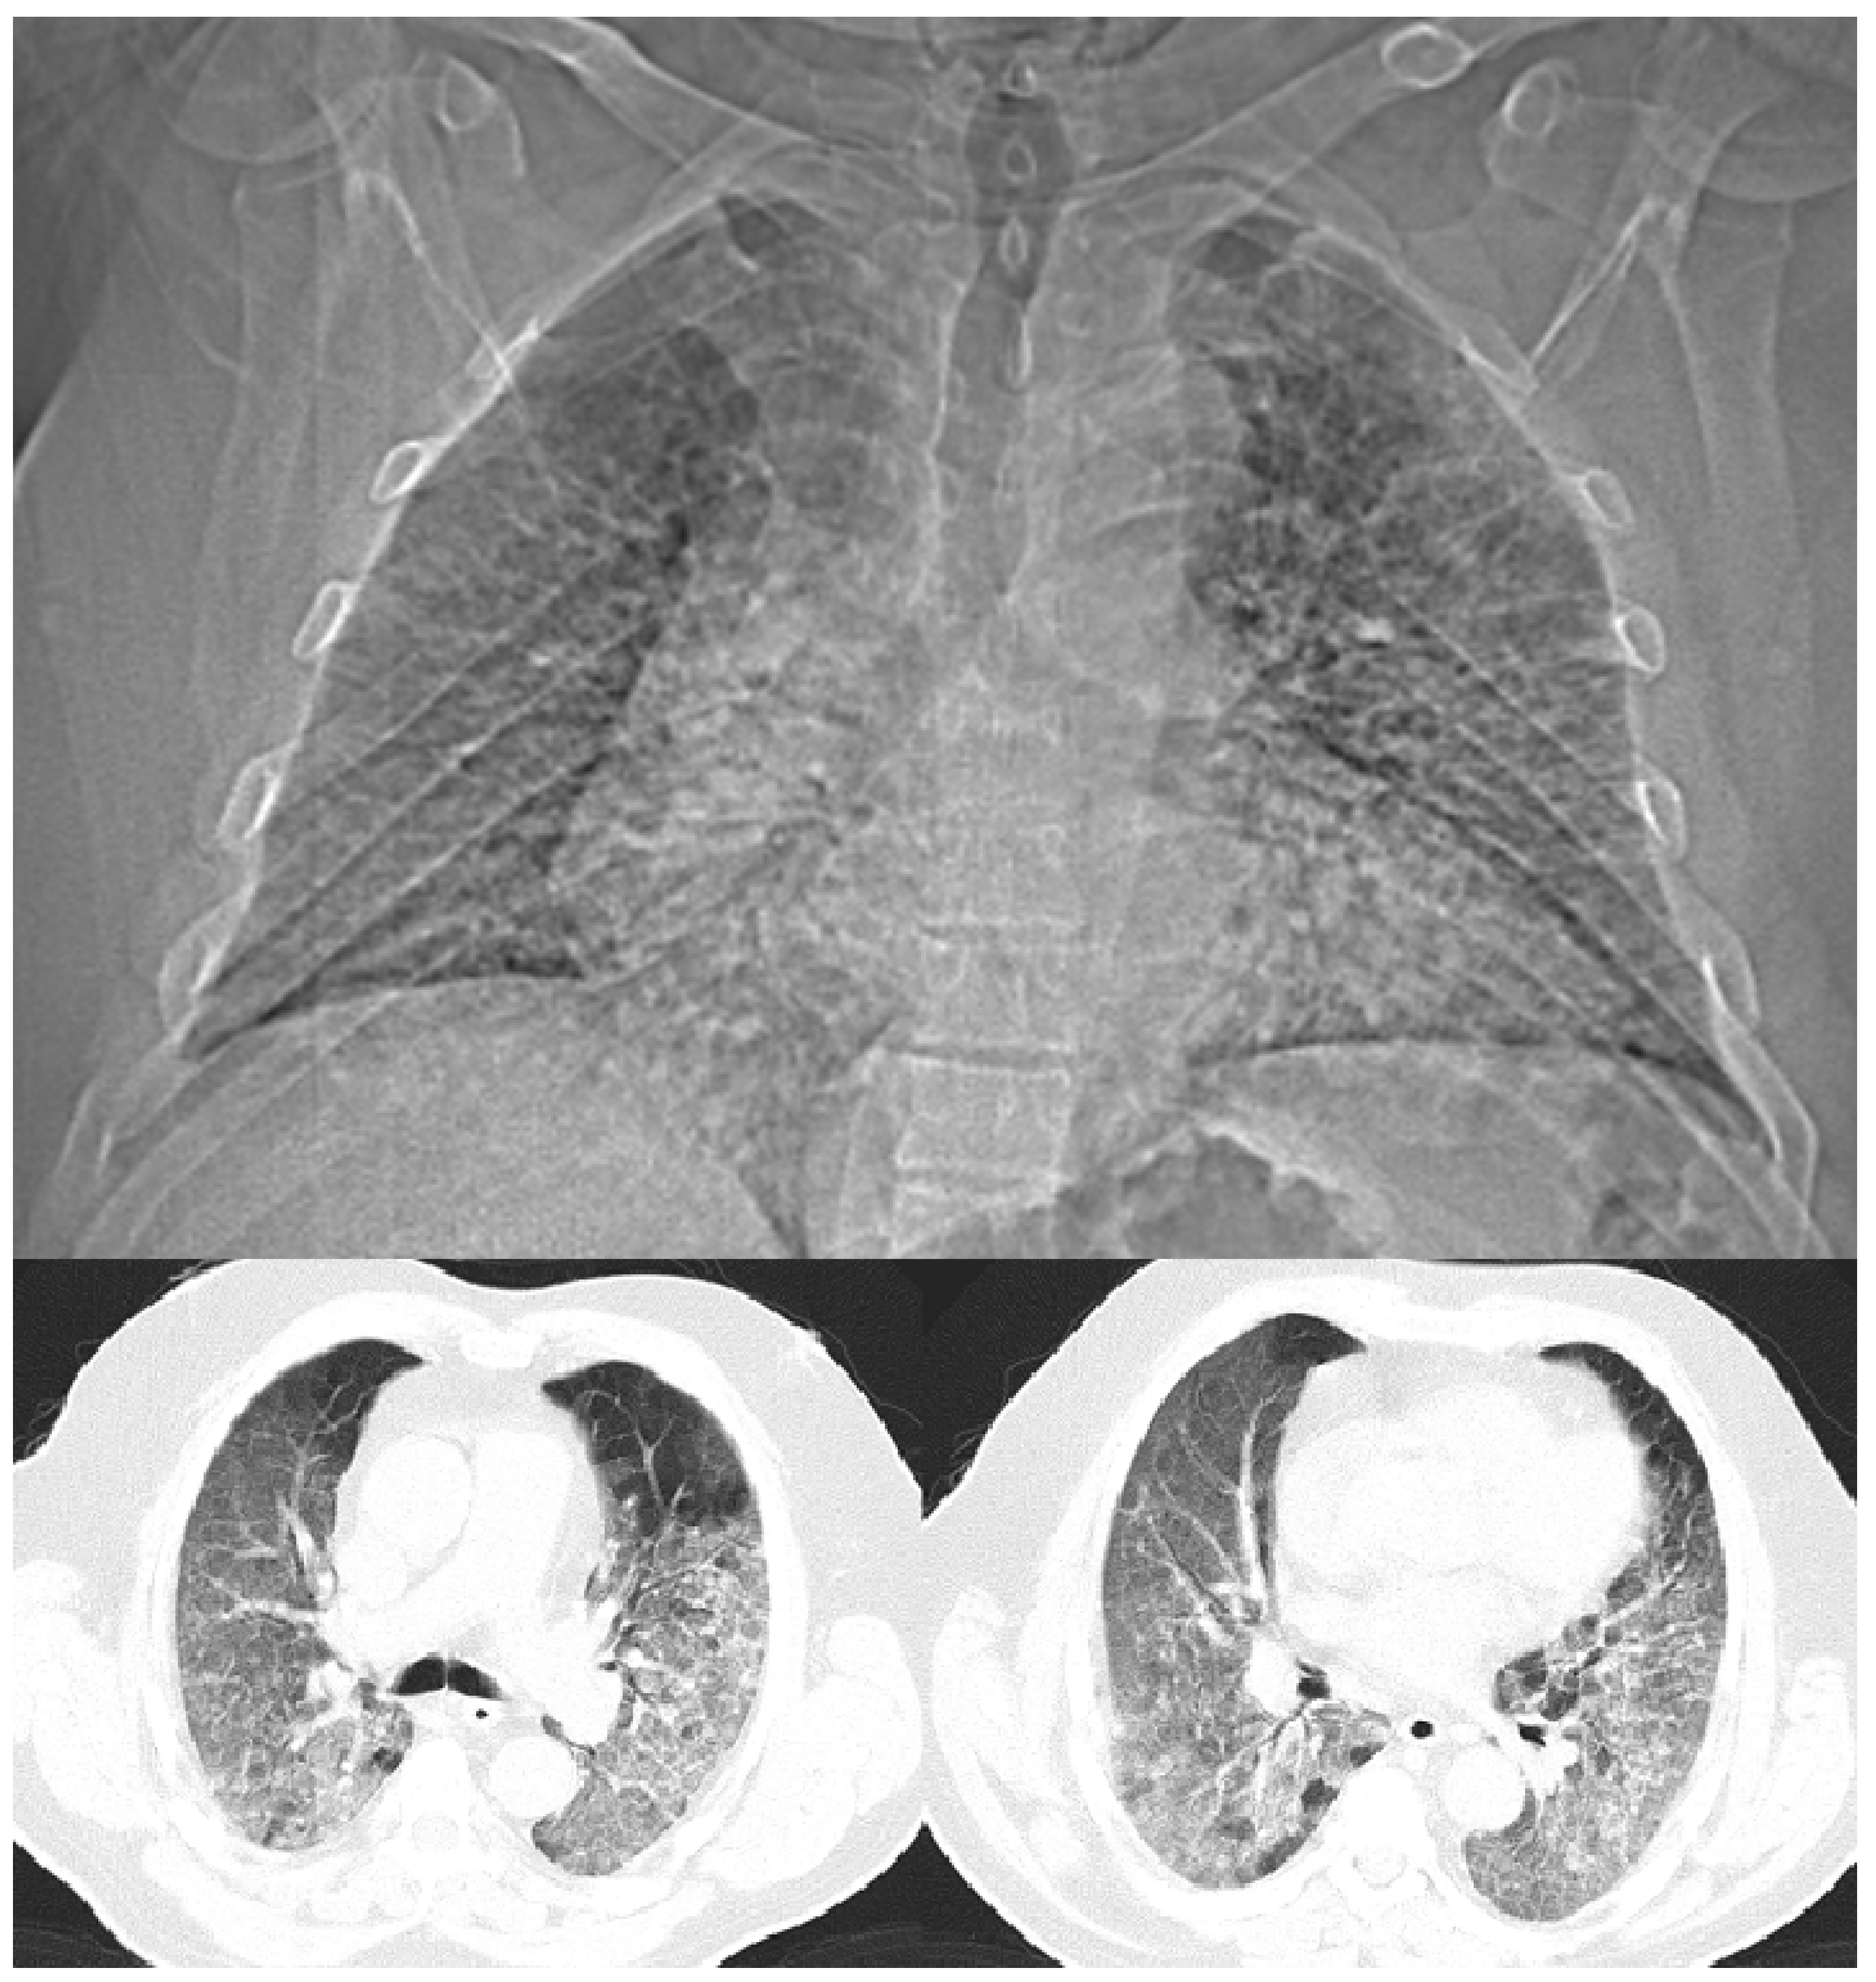

Onset of the Disease

An Accidental Overdose of Colchicine Results in Immediate Recovery of the Patient

Discussion